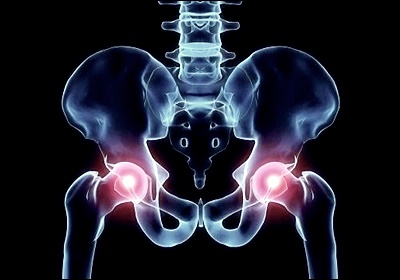

고관절 통증의 주요 원인

고관절 통증의 원인은 매우 다양합니다. 가장 흔한 원인으로는 퇴행성 관절염을 들 수 있습니다. 나이가 들면서 관절 연골이 닳아 없어지면서 발생하는 이 질환은 점진적인 통증과 뻣뻣함을 유발합니다. 또 다른 주요 원인으로는 고관절 충돌 증후군이 있는데, 이는 대퇴골 머리와 비구 사이의 비정상적인 접촉으로 인해 발생합니다. 류마티스 관절염, 골다공증으로 인한 골절, 활액막염, 건염 등도 고관절 통증을 일으킬 수 있습니다. 때로는 요추의 문제가 고관절 통증으로 나타나기도 하므로, 정확한 진단이 중요합니다.